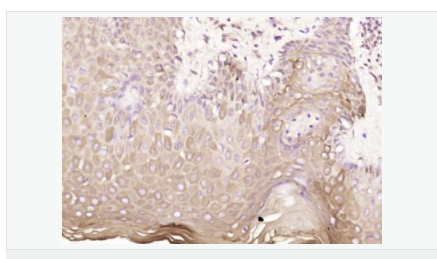

| 产品应用 | WB=1:500-2000 ELISA=1:5000-10000 IHC-P=1:100-500 IHC-F=1:100-500 ICC=1:100-500 IF=1:100-500 (石蜡切片需做抗原修复) not yet tested in other applications. optimal dilutions/concentrations should be determined by the end user. |

| 免 疫 原 | KLH conjugated synthetic peptide derived from human Ataxin 3:51-150/364 |